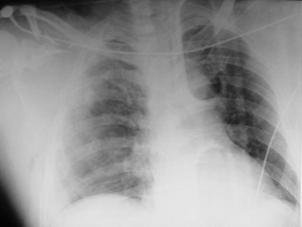

Traumatism toracic deschis Hemotorace stang masiv

Hemotorace stang masiv Hemotorace stang masiv

Hemotorace

drept masiv Hemotorace stang

Imagine CT Radiografie efectuata in ortostatism